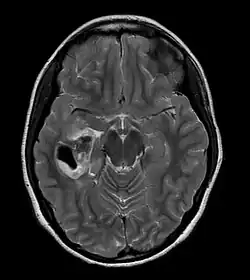

Badania neuroobrazowe

W tomografii komputerowej PXA ma postać powierzchownie leżącego guza, dobrze odgraniczonego, zajmującego opony miękkie, rzadko naciekającego oponę twardą i kości. W badaniu angiograficznym widać małe unaczynienie guza, jednak efekt wzmocnienia występuje. W MRI T1-zależnym guz jest izointensywny, w obrazach T2-zależnych lekko hiperintensywny, w całości ulega wzmocnieniu kontrastowemu.